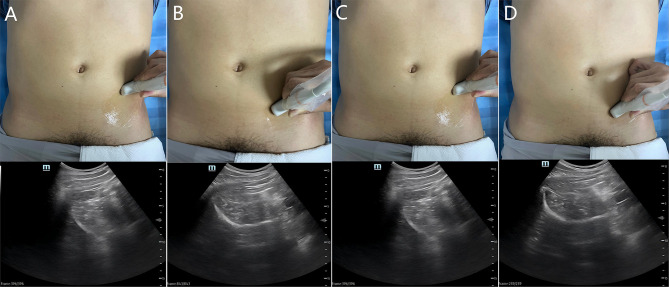

囊周神经群阻滞(PENG)是一种用于急性疼痛管理的区域麻醉技术,已成为急诊下肢骨折,特别是髋部损伤的常用麻醉方法。虽然目前的证据主要来自术后随机试验和病例系列,但最近的临床报告结果支持手术前在紧急情况下使用PENG阻滞快速镇痛40-60%的疼痛评分降低和保持运动功能。本综述综合了文献中的机制见解和临床结果,比较了髋关节囊的靶向感觉阻滞、PENG阻滞与全身性阿片类药物(有引起呼吸抑制的风险)和髂筋膜阻滞(可引起运动障碍)。彭阻断的主要优点包括显著的阿片类药物节约作用(吗啡使用减少50-70%)和几乎没有运动并发症。标准化的超声引导方案可以解决与解剖变异性相关的挑战。来自病例报告的初步证据表明,彭阻滞对骨盆和股骨干骨折有效,尽管需要多中心试验来确定最佳剂量和长期功能结果。这一证据表明,PENG阻断可以作为一种有希望的紧急干预措施,但需要进一步改进方案。

The pericapsular nerve group (PENG) block is a regional anaesthesia technique for acute pain management that is becoming frequently employed for emergency lower limb fractures, particularly hip injuries. While current evidence has been predominantly derived from postoperative randomized trials and case series, the results of recent clinical reports support the preprocedural utility of the PENG block in emergency settings for rapid analgesia 40-60% pain score reduction and preservation of motor function. This review synthesizes mechanistic insights and clinical outcomes from the literature, comparing the targeted sensory blockade of the hip capsule with the PENG block with that of systemic opioids (which risks inducing respiratory depression) and fascia iliaca block (which can induce motor impairment). Key advantages of PENG blockade include significant opioid-sparing effects (50-70% reduction morphine use) and almost no motor complications. Standardized ultrasound-guided protocols can address challenges related to anatomical variability. Preliminary evidence from case reports suggests that the efficacy of the PENG block to pelvic and femoral shaft fractures, although multicentre trials are needed to establish optimal doses and long-term functional outcomes. This evidence indicates that PENG blockade could serve as a promising emergency intervention, but further protocol refinement is warranted.